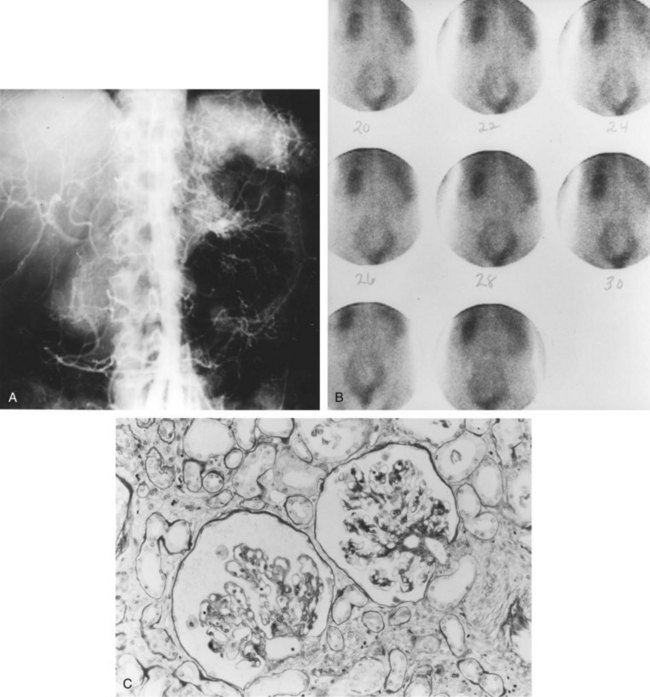

Approximately 70% of all renovascular lesions are caused by atherosclerosis (Novick et al, 1996). This disease may be limited to the renal artery but more commonly is a manifestation of generalized atherosclerosis, involving the abdominal aorta and coronary, cerebral, and lower extremity vessels. Atherosclerotic stenosis usually occurs in the proximal 2 cm of the renal artery, and distal arterial or branch involvement is distinctly uncommon. Owing to the proximal location of these lesions, oblique aortic views are often needed to adequately visualize the area of stenosis. The lesion involves the intima of the artery and, in two thirds of the cases, presents as an eccentric plaque (Fig. 39–1); in the remainder, the vessel is circumferentially involved, with narrowing of the lumen and destruction of the intima. Dissecting hematomas frequently complicate this disease, sometimes resulting in thrombosis of the entire vessel.

Figure 39–1 Histopathologic appearance of eccentric atherosclerotic plaque causing renal artery stenosis.

IN is the result of chronic hypoperfusion of the total functioning renal mass. This occurs in the setting of bilateral severe stenosis or stenosis to a functionally or anatomically solitary kidney. The pathophysiology of renal injury as a result of chronic ischemia is poorly understood. This injury is not simply cell death due to a lack of oxygen and nutrients, because the oxygen demand of the kidney never exceeds the supply. Experiments studying the effects of acute renal ischemia do not lend themselves to the explanation of chronic ischemic injury. For ischemic injury to occur, the reduction in renal blood flow needs to exceed the compensatory ability of the kidneys. Renal autoregulation fails to maintain the GFR when renal perfusion decreases below 70 to 80 mm Hg. This occurs when the luminal diameter of the renal artery is stenosed by more than 70% of the original size. At this point, the stenosis becomes hemodynamically significant, resulting in a gradual deterioration of the GFR with an accompanying rise in the serum creatinine level (Fig. 39–7).

Although the exact mechanisms through which chronic ischemic injury of the kidneys occur are not clear, the resulting structural changes within the chronically ischemic kidney have been well identified. Tubular changes are usually most prominent, in the form of patchy tubular necrosis and atrophy. Glomeruli decrease in size, with wrinkling of the glomerular tuft and thickening of the Bowman capsule. Localized or global glomerular sclerosis is also seen. Hypercellularity of the juxtaglomerular apparatus is commonly seen. Blood vessels show the effects of comorbid conditions, such as essential hypertension, diabetes, and hyperlipidemia, with arteriolar thickening and hyalinosis.

Atheromatous fragments lodged in blood vessels are highly thrombogenic, leading to occlusion of the vessels in which they lodge, and, at the same time, an inflammatory reaction and fibrosis are incited. Cholesterol crystals can remain histologically detectable in blood vessels for up to 9 months after the event. Diagnosis of atheroembolism is made by examination of biopsy samples from the affected tissue, most commonly skin, muscle, or kidney. Cholesterol microemboli are seen within the renal vasculature (needle-shaped cholesterol crystals, which appear birefringent on frozen section and are dissolved by the solvents used in permanent sections, leaving empty cholesterol clefts) and generally portend a poorer prognosis. In a study of 44 patients from the Cleveland Clinic, findings reflective of atheroembolism were identified on intraoperative biopsy of 16 patients (36%) at the time of open surgical renal revascularization. Patients with atheroembolism had a significantly decreased 5-year survival (54% versus 85%), compared with patients who did not exhibit histologic evidence of atheroembolism. Patients with atheroembolism had a significantly higher incidence of postoperative atherosclerotic complications as well as renal and renovascular complications (Krishnamurthi et al, 1999).